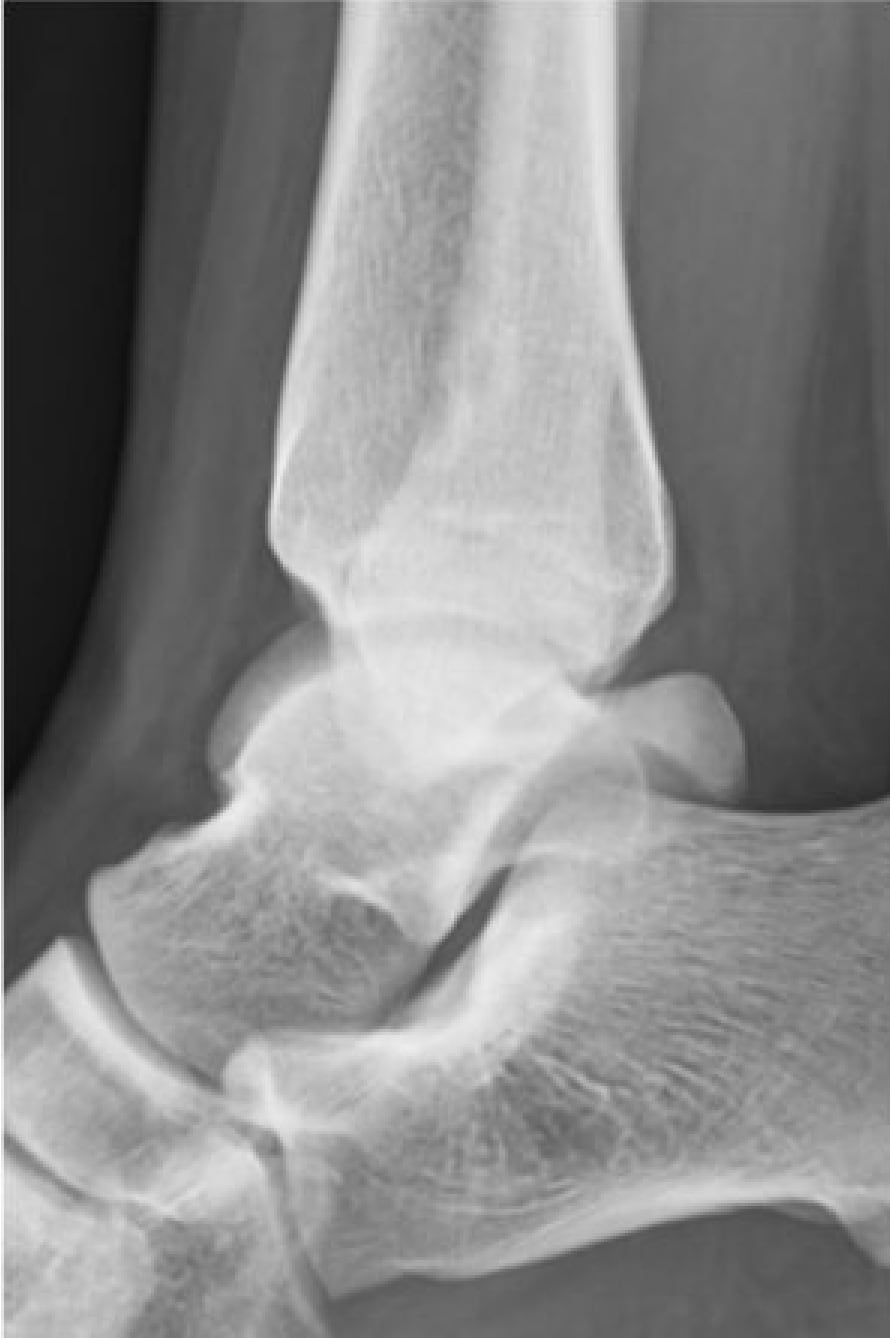

2020-12-09 スポーツ整形 ページ内リンク 後方インピンジメント症候群(三角骨障害)【スポーツ整形外科】 後方インピンジメント症候群(三角骨障害)【スポーツ整形外科】 サッカーやラグビーのキック動作やクラシックバレエのポアント肢位で足関節後方の骨が衝突して疼痛が発生する。⇒鏡視下切除により症状消失。 術前 術後 杉本 武 副院長/スポーツ整形外科センター長 整形外科スポーツ整形 詳しく見る 関連ページ スポーツ整形 一覧へ戻る